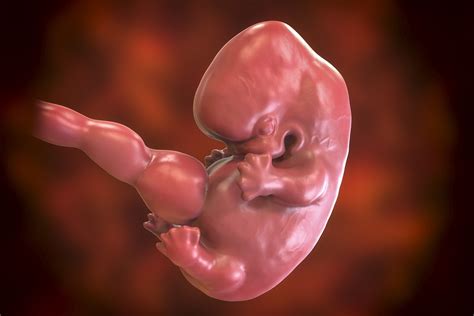

A terhesség kilenc hónapja alatt a magzati fejlődést nagyjából két szakaszra lehet osztani: az első két hónapban az embrionális szakasz, majd ezt követi a magzati szakasz.

A magzati szakasz kezdetével lényegesen lecsökken a spontán vetélés veszélye (minden száz felismert terhességből 12-15 végződik vetéléssel a terhesség első felében).

Az embrionális kor végére felismerhetők a születendő gyermek főbb szervei, mint a kezek, lábak, az agy, belső szervek stb.

A magzat agyának aktivitását a terhesség 5. és 6. hetében lehet először észlelni, bár ekkor még ez nem jelenti a tudatosság kezdetét.